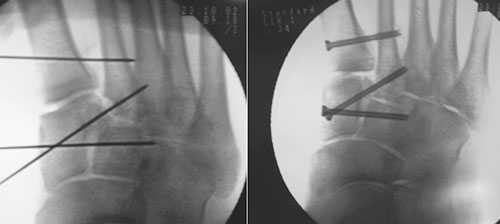

(Справа) При КТ в сагиттальной плоскости визуализируется вывих 5-й плюсневой кости в сторону подошвы. Необычная травма была получена при езде на велосипеде. (Слева) При рентгенографии среднего отдела стопы в передне-задней проекции определяется односторонний вывих сустава Лисфранка: 1-5 плюсневые кости смещены латерально, переломы не выявляются.

(Справа) Этому же пациенту были выполнены открытая репозиция и внутренний остеосинтез. При рентгенографии среднего отдела стопы в передне-задней проекции видно, что для обеспечения стабильности суставов требуется фиксация множества костей. Следует отметить наличие винта, который выполняет функцию поврежденной связки Лисфранка.

При смещении более 2 мм, нестабильности при функциональных тестах – рекомендовано открытое устранение вывиха с жёсткой фиксацией винтами или пластинами. Используются один или два продольных доступа в 1 и 2 межплюсневых промежутках. После обнажения первого предплюсне-плюсневого сустава первым этапом устраняется межклиновидная нестабильность, вторым этапом устраняется предплюсне-плюсневая нестабильность. В послеоперационном периоде сразу начинается разработка активного объёма движений. Нагрузку на стопу начинают постепенно, с тем чтобы полностью её восстановить к 6-8 неделе. Удаление спиц Киршнера производится через 6-8 недель, компрессирующих винтов через 3-6 месяцев. Возвращение к полной физической активности не ранее 9-12 месяцев после операции.

Открытое вправление вывиха, трансартикулярная фиксация 1-2-3 предплюсне-плюсневых суставов винтами.